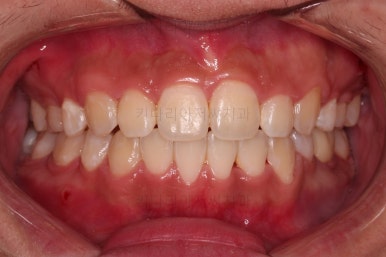

초진 시 입안의 모습입니다.

앞니가 많이 삐뚤고, 송곳니가 부각되어 덧니처럼 보이네요.